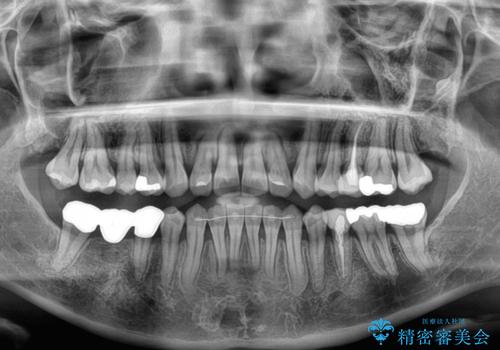

- 上下前歯のデコボコとクロスバイトを気にして来院された患者様です。

治療済みの処置歯が多いため、インビザラインを用いて矯正治療を行うこととしました。

下顎臼歯部にブリッジが装着されており、移動不可のため、IPR(歯と歯の間を削る)と歯列全体を拡大させることで、歯並びを整えていくこととしました。

インビザライン特有の奥歯の噛みにくさが治療後半に発現しましたが、無事に終了させることができました。